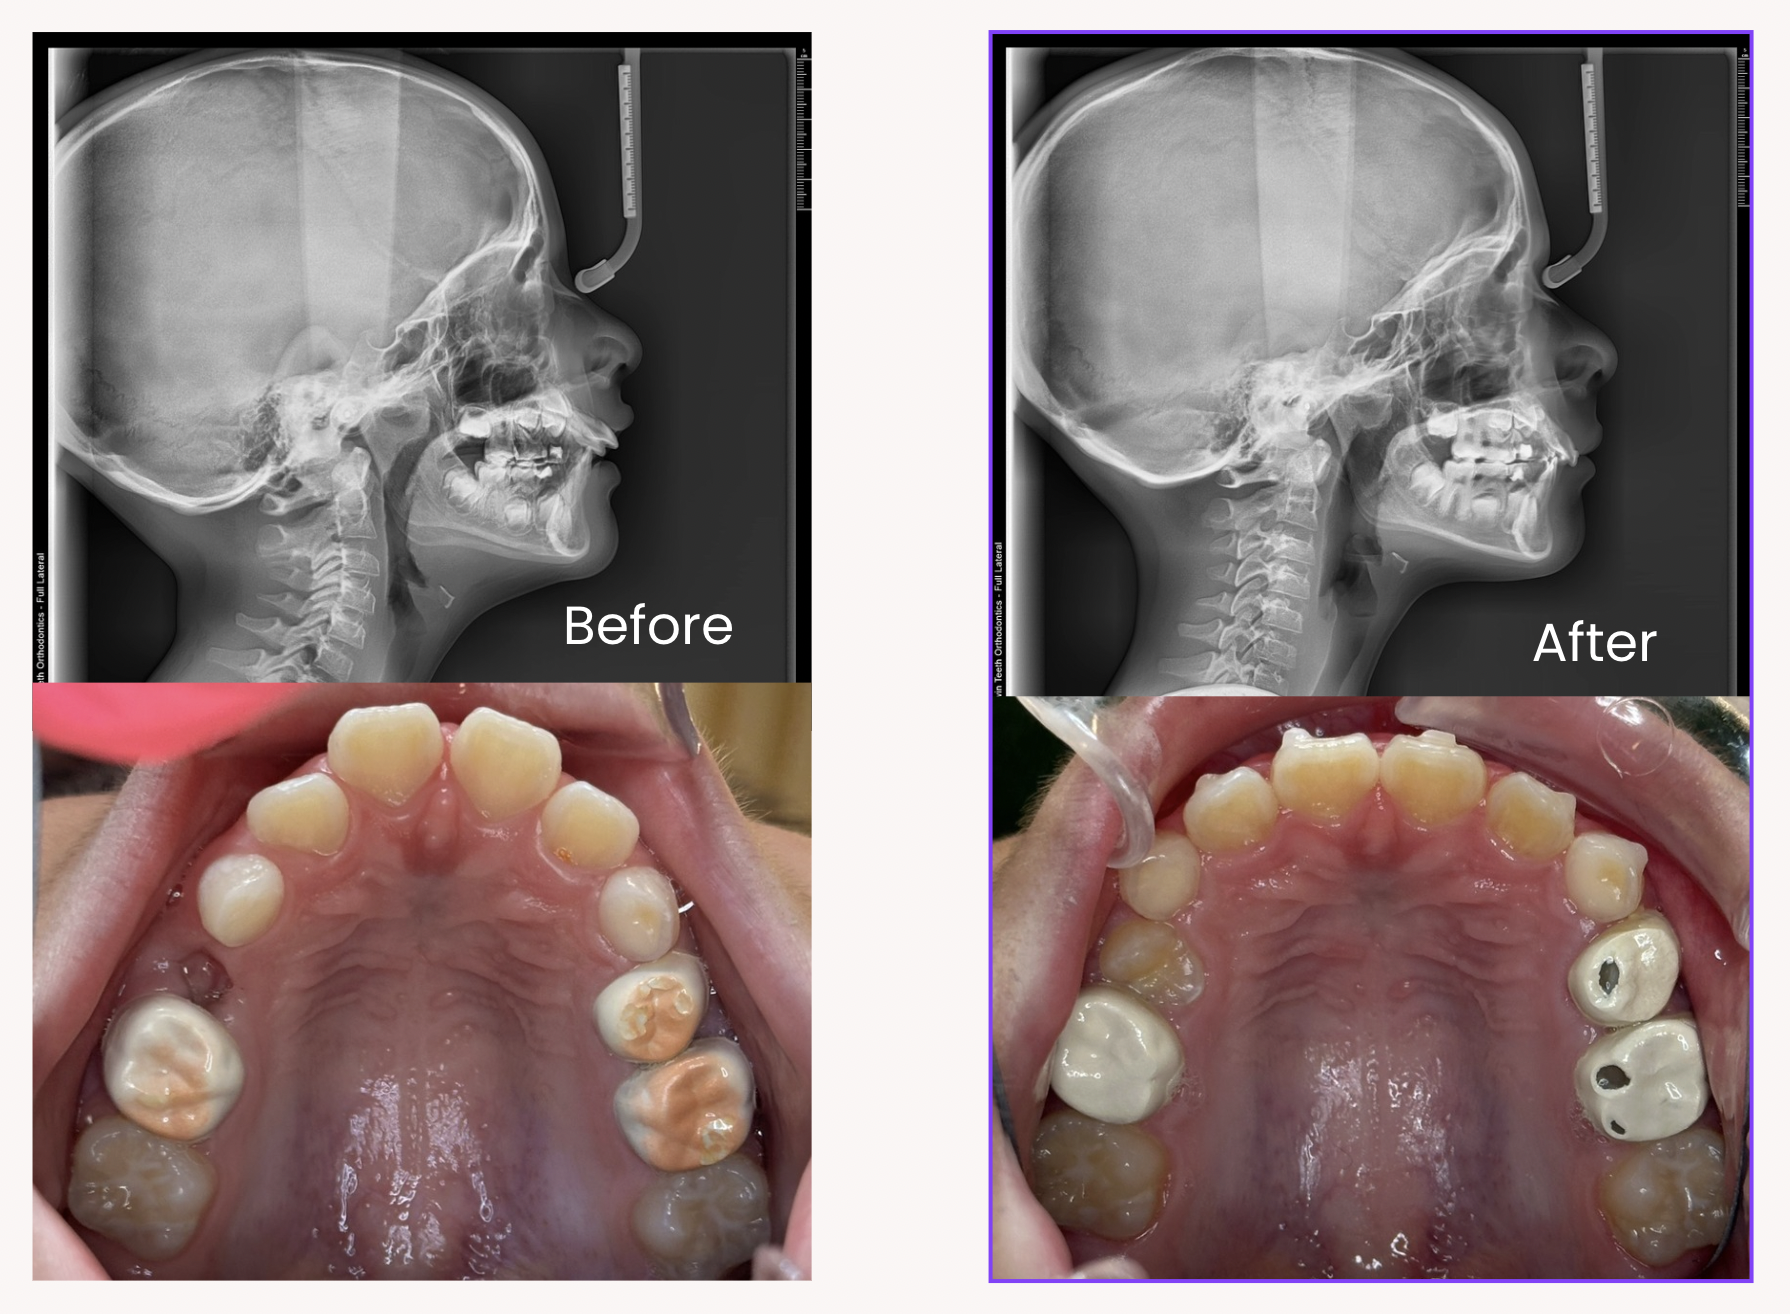

Airway Before and After

Expansion for airway improvement, adenoid shrinkage, posture improvement, sleep-disordered breathing symptom relief